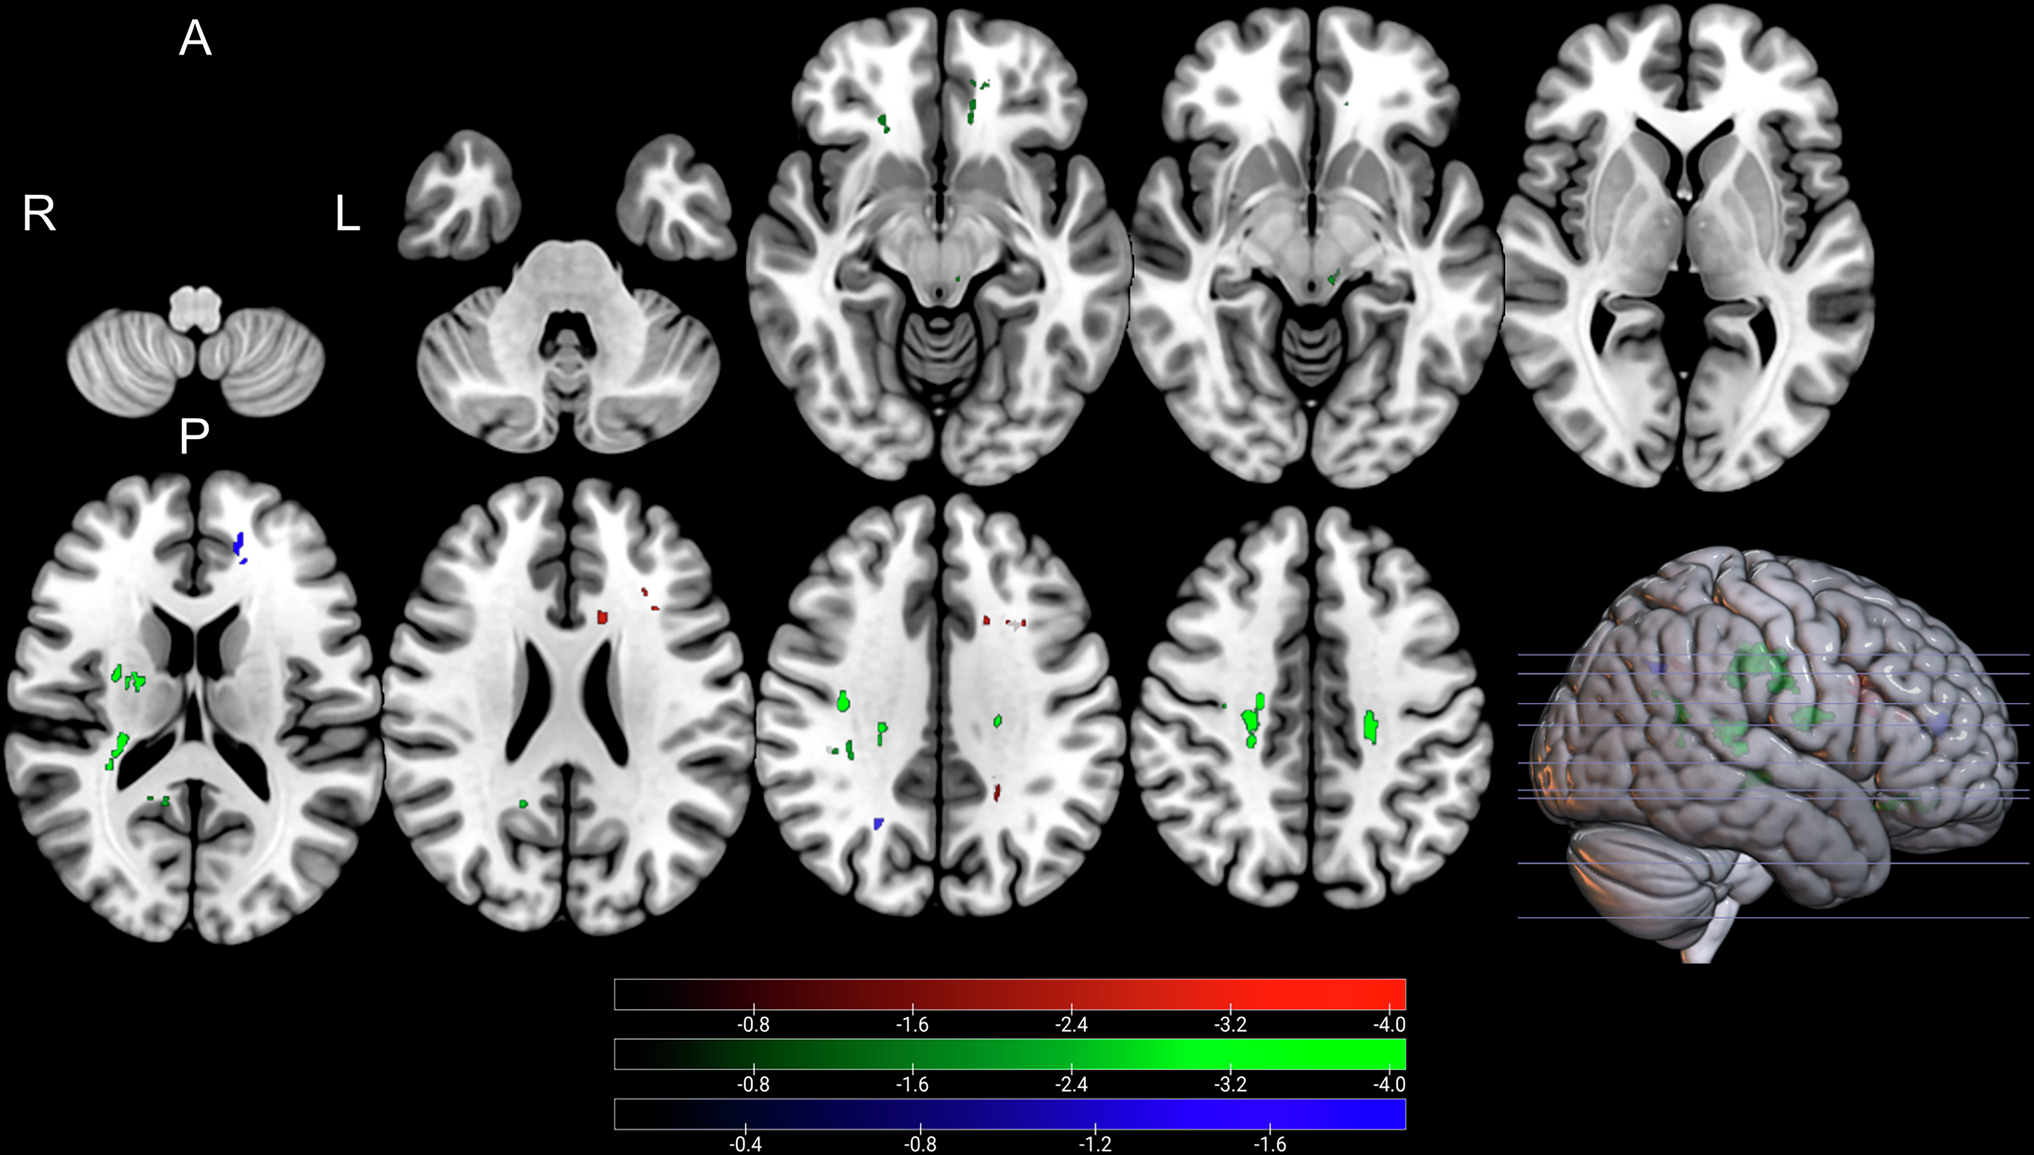

Fig. 3

Clusters with a negative association between PD patients’ ODI-values and postoperative change in UPDRS (red), time spent in ON (green), and time spent in OFF (blue), as revealed by the whole brain analysis. P-values were corrected for multiple comparisons using a permutation-based approach. Clusterwise P-Values were corrected for multiple comparisons using a permutation-based approach and shown as the negative decadic logarithm of the p-value.